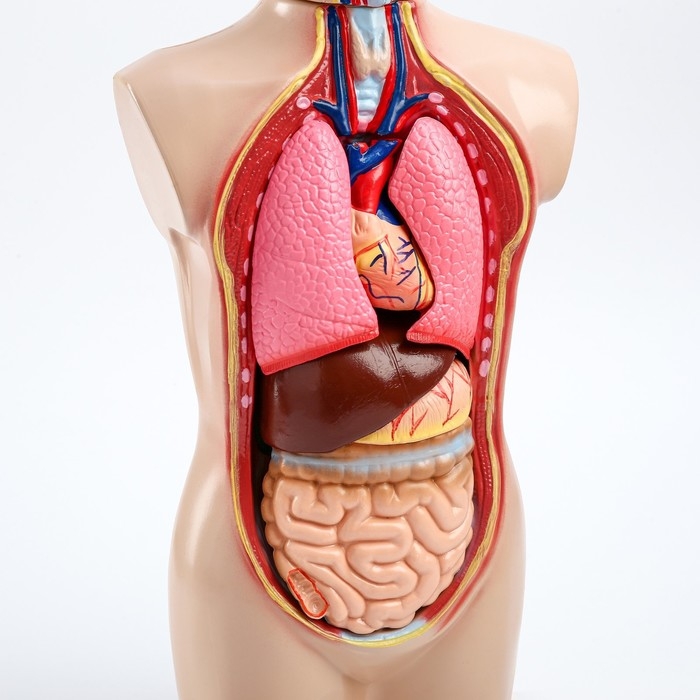

Анатомические модели

ЕКБ 39

No Brand, артикул: 7072361